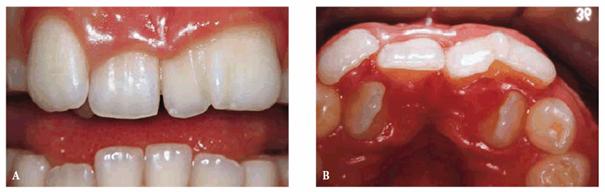

A male patient, 5 years, 8 months old.

PROBLEM: Occasionally, parents complain about discoloration of their

children's primary teeth, or the discoloration may go unnoticed. Discoloration

of primary teeth, as in this case, may be due to slight damage, such as

concussion or subluxation. If discoloration continues without pulp

obliteration, there is a possibility of pulp necrosis. Because of the original

trauma, a malformation of the anatomic crown of teeth #8 and #9 is observed.

TREATMENT: After the complete eruption of the two upper central

incisors, the pigmentation (hypoplasia) of the teeth is restored with composite

resins.

RESULT: Because enamel hypoplasia is superficial damage, it can be

easily and esthetically resolved (Figures 27-5A

and B).

Figure 27-5A and B: Due to a trauma to primary teeth, a malformation of the anatomic crown of teeth #8 and #9 is observed (hypoplasia). Teeth are restored with composite resin.